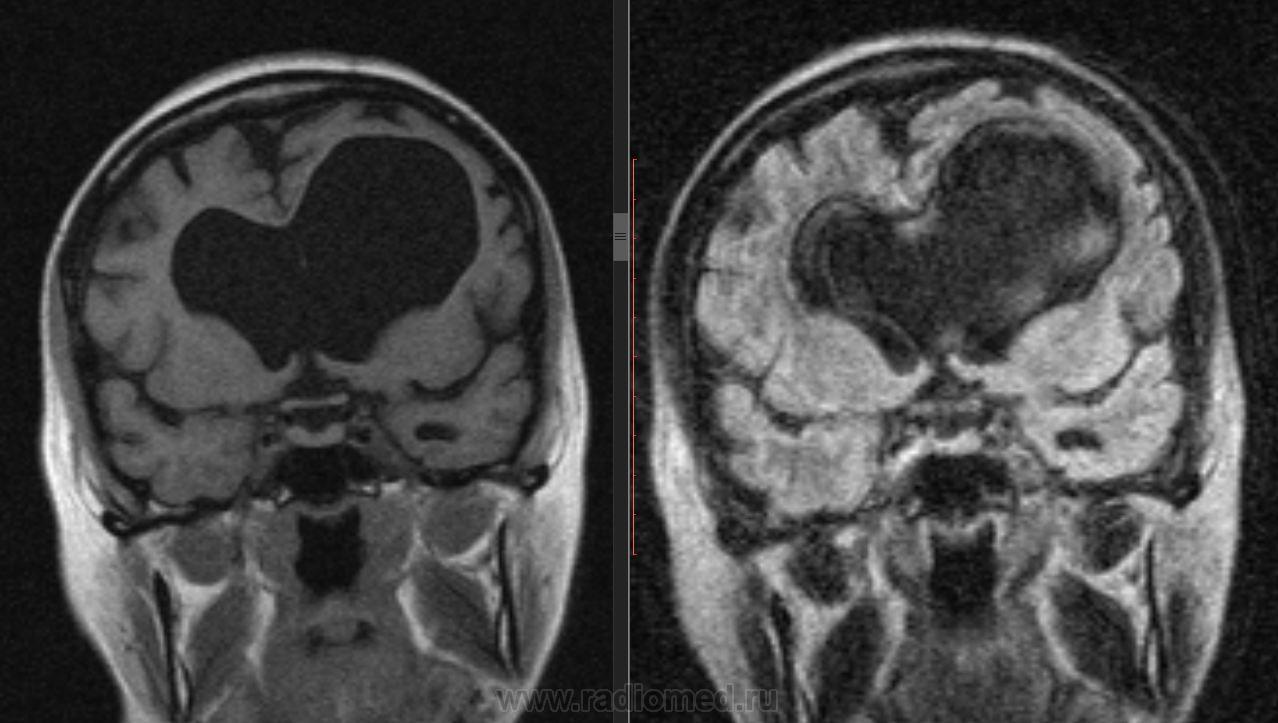

Женщина 53 года... Не могу найти причину гидроцефалии...

Окклюзия на уровне сильвиева водопровода. А причина...?

Не вижу окклюзии на уровне Сильвиева водопровода. Внутренняя неокклюзионная гидроцефалия.

А вообще-то, от рентгенолога требуется указать на наличие или отсутствие явных признаков повышения внутрижелудочкового давления (перивентрикулярный отек), а в случае наличия такового - выявить уровень и причину окклюзии. Здесь открытая, преимущественно внутренняя гидроцефалия, т.е. окклюзии нет, давление в желудочках условно считается  нормальным, и вмешательства нейрохирурга не требует.

А если рассуждать о причинах - то это, скорее всего, перинатальное гипоксически-ишемическое или травматическое поражение, приводящее к затруднению резорбции ликвора в подпаутинных пространствах. Пациентка живет с этой гидроцефалией всю жизнь.

Там еще и киста прозрачной перегородки, кстати! Не могу подтвердить это литературой, но по моим собственным наблюдениям, у недоношенных детей или у детей с перинатальными проблемами листки прозрачной перегородки часто остаются несращенными.

Давление в желудочках "условно нормальное", но дно третьего желудочка пролабирует в селлярную область:)

Может в данном случае вариант нормотензивной гидроцефалии? (есть ли сочетание деменции, нарушений ходьбы и недержания мочи?

Про сочетание вышеописанных признаков достоверно сказать не чего не могу, известно что неврологические проблемы около 2-х лет. В данном случае меня смутила ассиметрия боковых желудочков и пролабирование третьего желудочка, нормальный четвертый желудочек... В общем стаж мой в МРТ очень маленький и я боялся пропустить оклюзию на уровне водопровода.